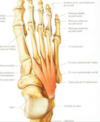

Identifier les muscles extrinsèques du pied (encadré)

Nommez les muscles présents sur l'image (vue dorsale)

Nommes les structures présentés dans l'image (vue plantaire)

Nommez les muscles (les lignes du haut seulement) vue dorsale

1. Phalange distal de l’hallux 2. 1er métatarsien 3. Os cunéiforme médial 4. Os cunéiforme intermédiaire 5. Os naviculaire 6. Talus 7. Os cunéiforme latéral 8. Os cuboïde 9. Calcanéus